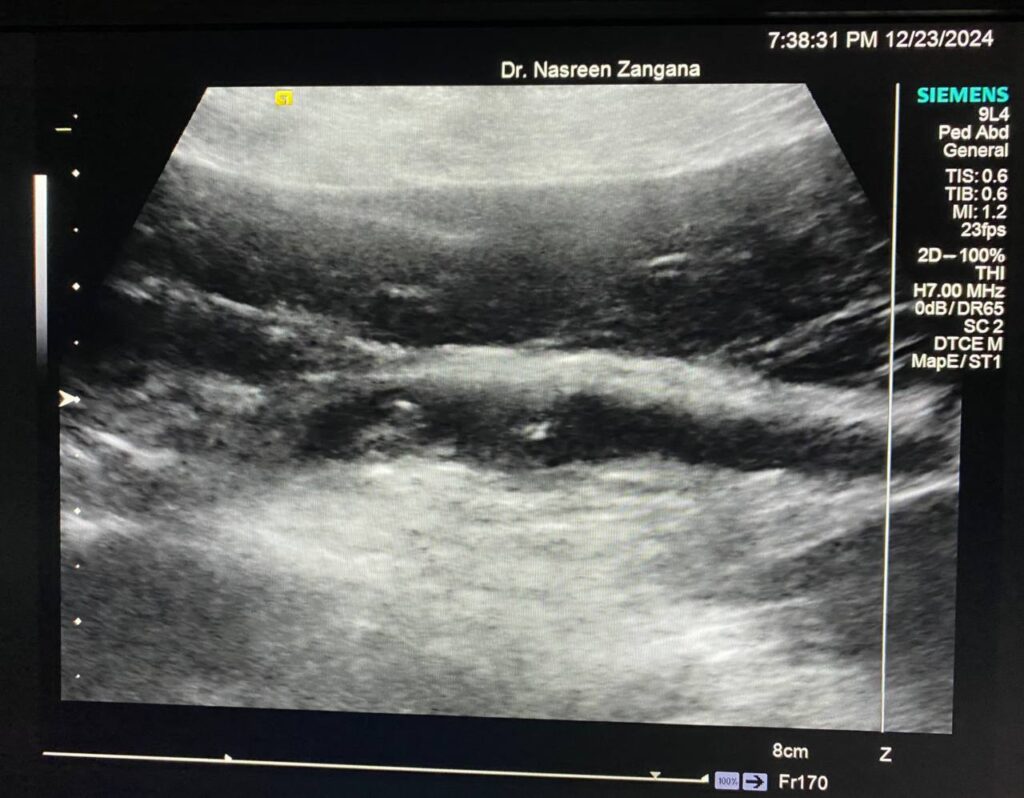

Diffuse dilated common bile duct 7.3mm , with presence of multiple echogenic foci within , the largest 3mm